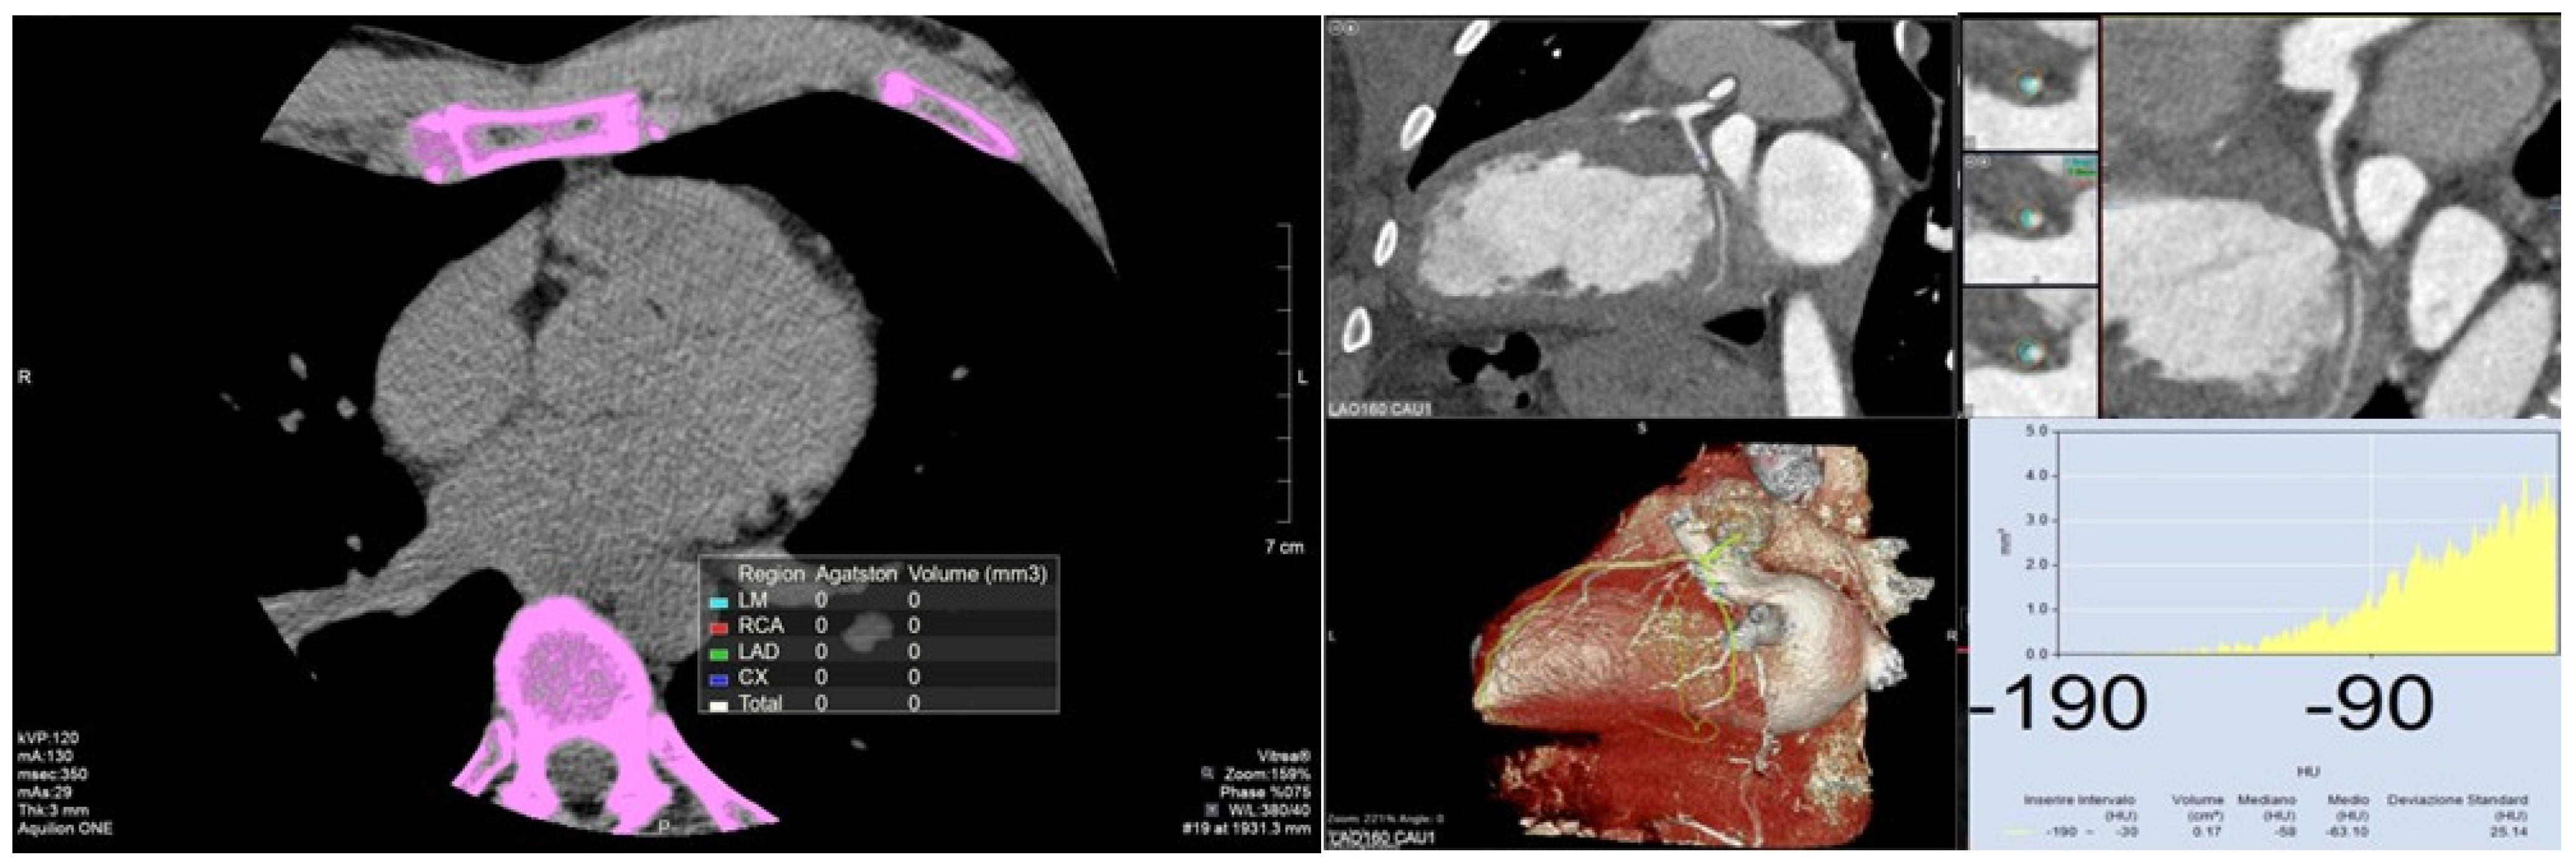

2. Coronary Calcium Score

2.1. Definition

2.2. Measurement

3. Perivascular Fat Attenuation Index

3.1. Definition

3.2. Measurement